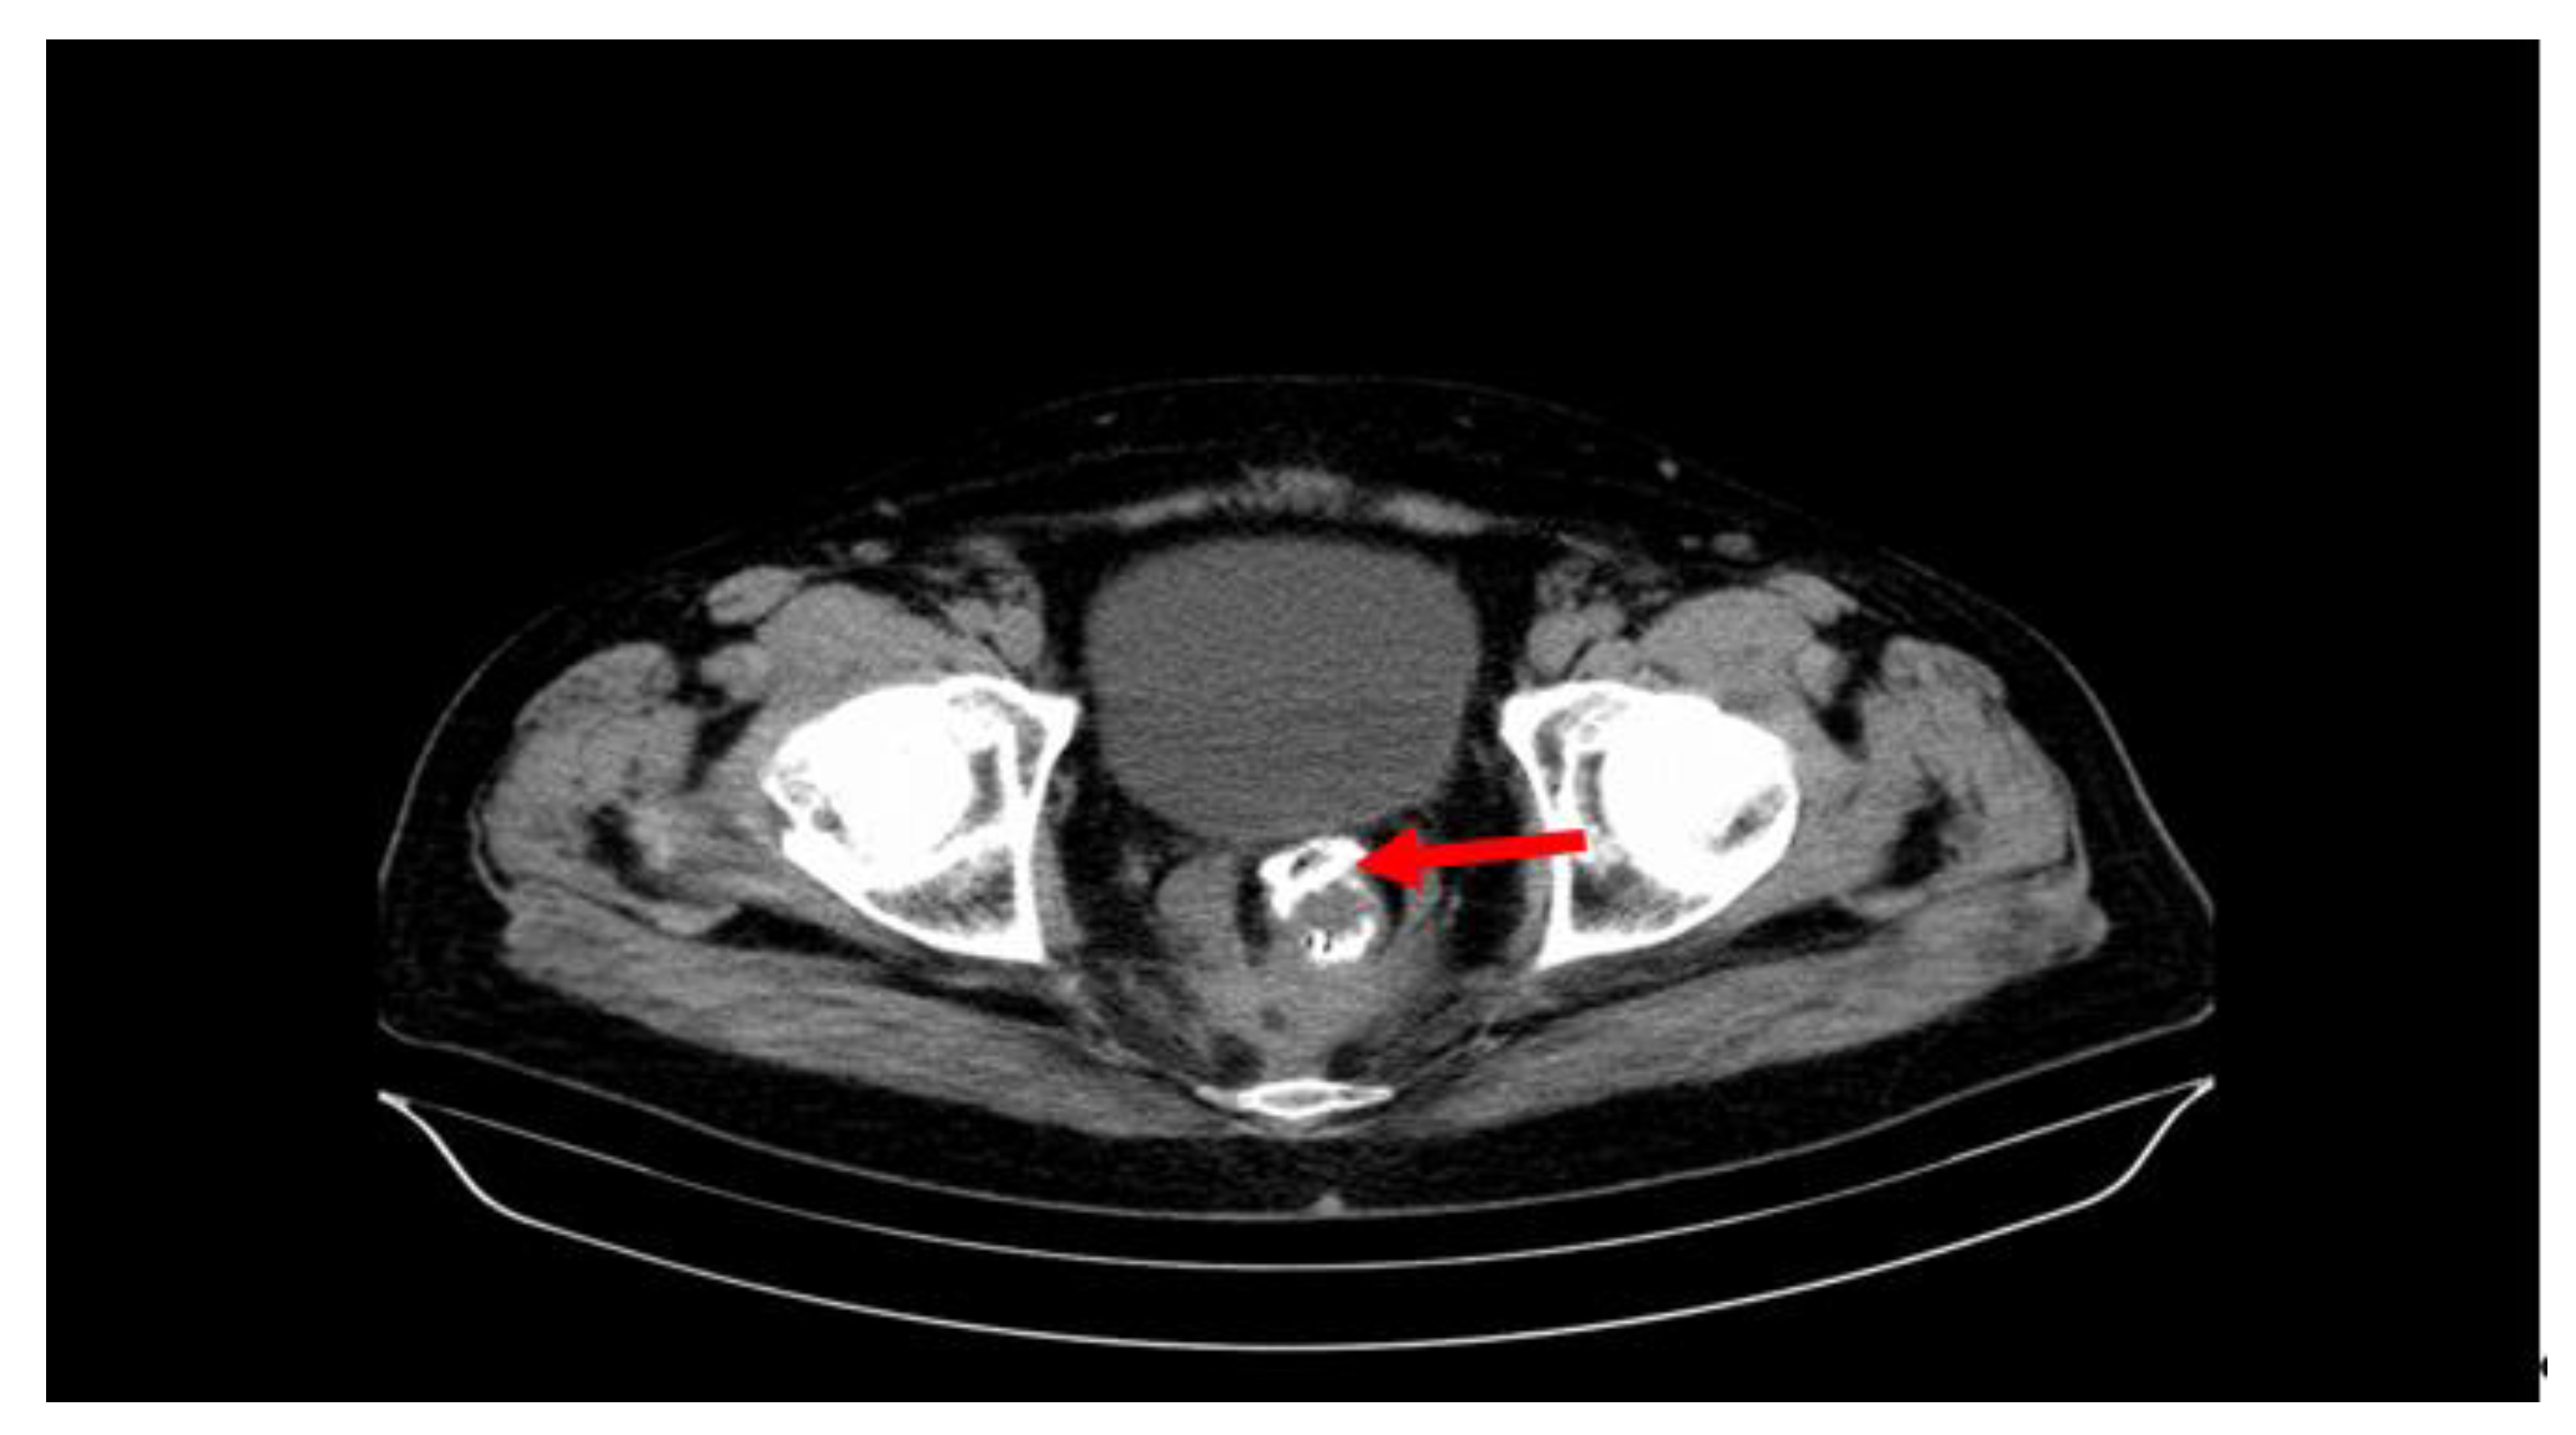

Table 1 lists the specific complications compared with the APER and LAR surgical procedures, performed either laparoscopically or classically, correlated with the rectal segments. Thus, at the level of the upper rectum, 34 surgical interventions (LAR) developed complications. Of these, we noted that 22 were performed laparoscopically and 12 classically. For these complications, conservative treatment was practiced in 28 patients (28.86%) (drainage under CT, lavage), and reinterventions were applied in six patients (6.18%) (laparotomy, drainage, lavage, abolition of the anastomosis, closure of the distal abutment, terminal colostomy). With regard to the neoplasms of the middle rectum, 19 surgical procedures (LAR) developed complications. Two were performed laparoscopically, and 17 were performed via the classic open route. The conservative treatment of complications was applied to 12 (12.37%) patients, and reinterventions were applied to seven (36.84%) patients. The surgical procedures performed at the level of the lower rectum (Figure 1) developed 44 specific complications (30 APER and 14 LAR). Thirteen operations were performed laparoscopically and 31 classically. The 30 cases (30.92%) after APER were only pelvic abscesses, and the 14 (14.43%) after LAR were postoperative abscesses and fistulas. Conservative treatment (drainage under CT, lavage) was performed in 28 patients (28.86%), and reintervention was performed in 16 patients (16.49%), namely laparotomy, drainage, lavage, abolition of the anastomosis and closure of the distal abutment, terminal colostomy, recto-vaginal fistula treatment, vaginal wall suture, etc.

Figure 1. Anterior colorectal anastomotic fistula (red arrow) after laparoscopic low anterior resection (LAR). The image shows the anastomosis clips arranged in a circle.